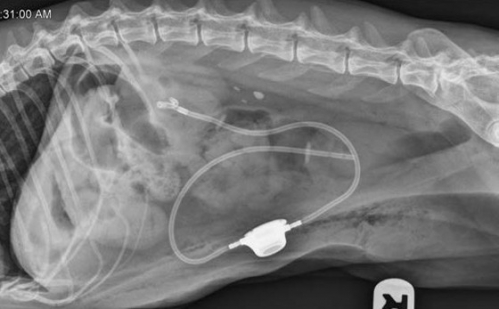

尿管結石をはじめとする尿管閉塞の手術の新たな手段として、特に猫において手術の難しい尿管とは別に腎臓と膀胱をバイパスする器具がアメリカで発売されています。尿管とは別ルートを確保できるため手術にまつわる様々な問題を回避できる可能性があり、困難を伴う尿管閉塞の治療を変えてくれるかもしれません。(下写真)